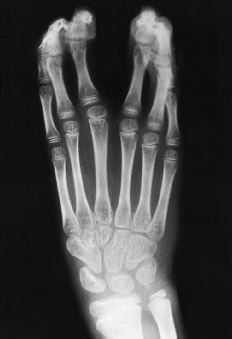

ABFigura 2. Caso 2. A: Radiografía de la mano izquierda mostrando seis radios trifalángicos en dos grupos en sindactilia con una comisura central. B: Aspecto clínico de los pies mostrando una polidactilia sin dedo gordo definido.